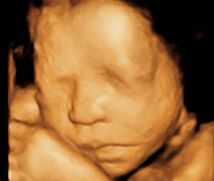

• -郑州万安妇产医院

相册

巴啦啦小魔仙 上传于 18-10-25 | 报错